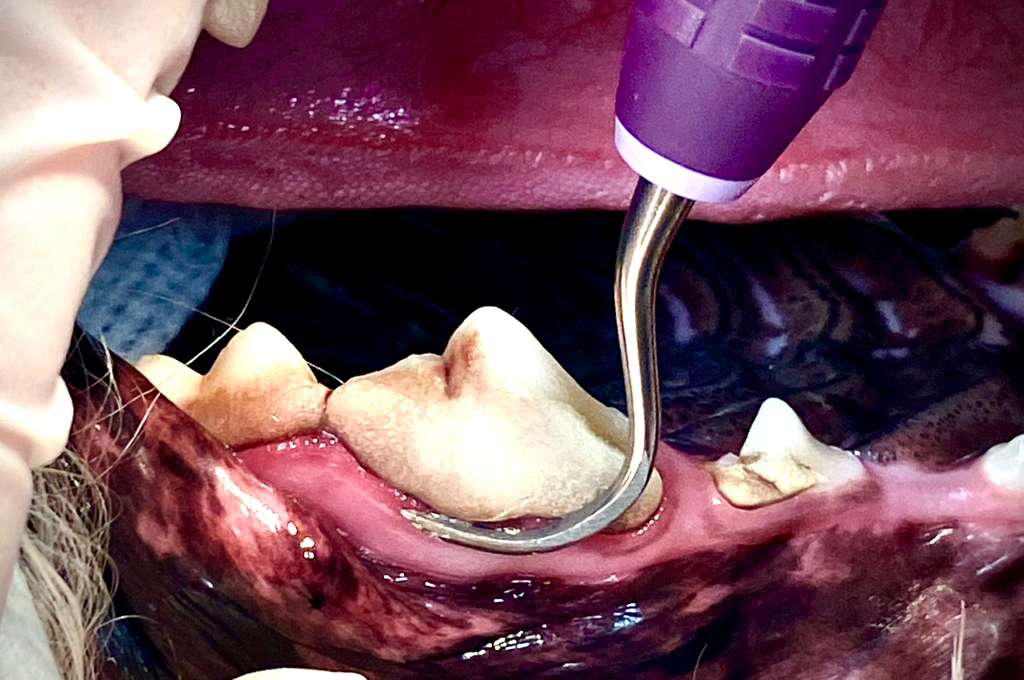

Periodontal Therapy

✔  Learn the correct way to perform a professional teeth cleaning ✔  Understand why proper dental care is important for pets ✔  Review the stages of periodontal disease ✔  Get familiar with required equipment and hand instruments ✔  Step-by-step teeth cleaning techniques with videos ✔  Learn charting techniques and abbreviations ✔  Tips for client education and marketing ✔  Doxirobe indications and proper placement ✔  Safe anesthesia protocols ✔  Equipment maintenance and instrument sharpening ✔  Guidance on home care products for pets ✔  Proper dental delivery unit maintenance ✔  Comprehensive notes provided for reference